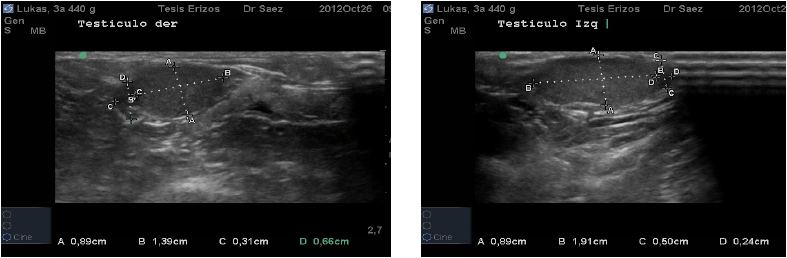

Topográficamente los testículos de los ETA se encuentran intra abdominales, vía ecográfica se observan caudo-ventralmente en el abdomen caudal y ubicados dentro de los recesos para-anales. El órgano presentó forma circular en el corte transverso, en la parte media, a diferencia del corte longitudinal donde se observaron ovalados. Su eje largo presentó una ligera oblicuidad siendo dorso-craneal/caudo-ventral. Su parénquima se presentó de mediana ecogenicidad, granulado fino y homogéneo. No se visualizó la línea ecogénica que describió Nyland [7] en el interior del testículo de animales domésticos, que correspondería al mediastino testicular (FIG. 4), esto podría deberse a que probablemente el mediastino en esta especie es menos fibroso o podría ser menos desarrollado y ubicarse en el extremo craneal del testículo, tal como ocurre en el equino (Equus caballus). Sería recomendable realizar un estudio morfoestructural para confirmar esta observación.

El epidídimo fue visualizado en el corte transverso de cada testículo. Se observó como una estructura circular, hipoecoica en relación al testículo, y en algunos casos, tendiendo a no generar ecos. Su ubicación fue variada, encontrándose en cinco individuos medial a cada testículo, en tres se localizó lateral a cada testículo y en dos casos, se visualizó el epidídimo lateral al testículo izquierdo y el epidídimo medial al testículo derecho. Esta ubicación variable sugiere que los testículos, dentro del abdomen, tienen cierto grado de movilidad, permitiendo así que se giren levemente, lo que ecográficamente se visualiza con el epidídimo lateral, medial o en algunos casos ambos lados, en relación al testículo (FIG. 5, 6 y 7).

Los resultados cuantitativos de morfometría fueron medidos en centímetros (cm) y expresados en promedios junto con desviación estándar (X ± DE). Se midió ancho, alto y largo de Testículo Izquierdo, y Testículo Derecho. En el caso del Epidídimo se midió ancho y alto de epidídimo en diez machos, ya que en uno de los pacientes no fue observable. En el 80% de los casos en el epidídimo predominó el ancho sobre el largo. Se midió el ancho, alto y largo de la Próstata. Los resultados se especifican en la TABLA III.